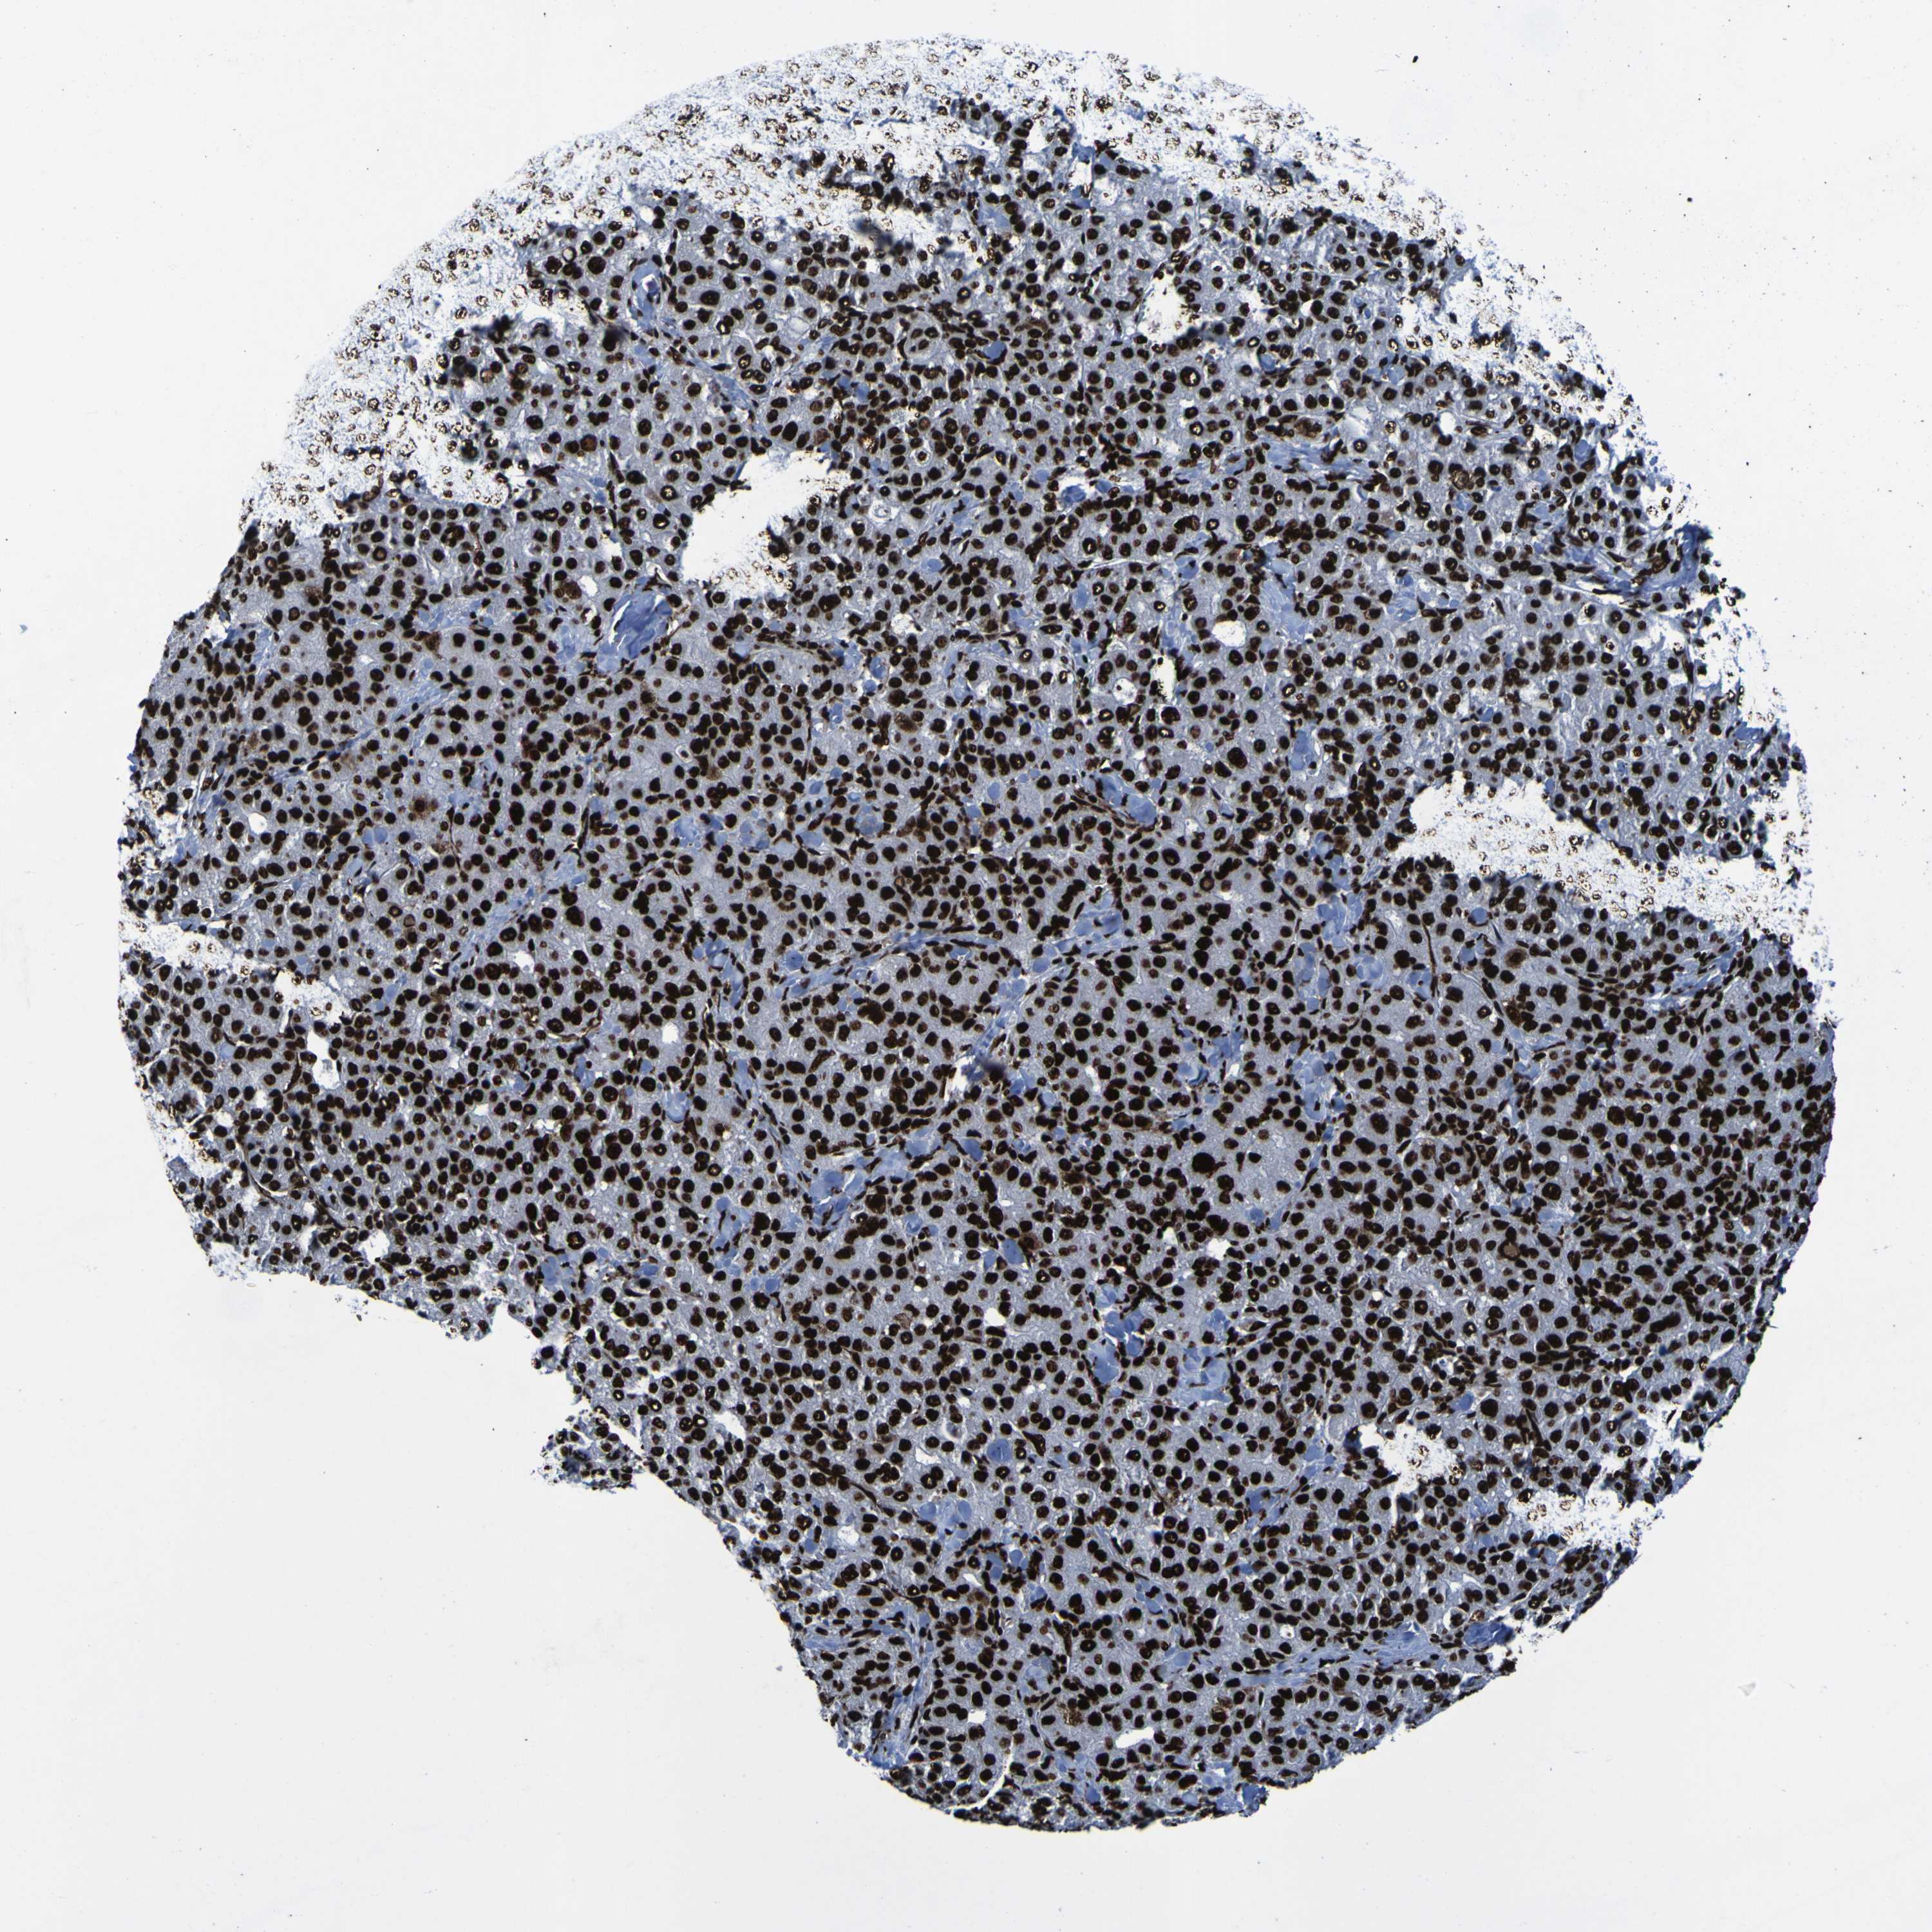

LIVER CANCER - Protein expressioni

A mouse-over function shows sample information and annotation data. Click on an image to view it in a full screen mode. Samples can be filtered based on level of antibody staining by selecting one or several of the following categories: high, medium, low and not detected. The assay and annotation is described here.

Note that samples used for immunohistochemistry by the Human Protein Atlas do not correspond to samples in the TCGA dataset.

Antibody stainingi

Antibody staining in the annotated cell types in the current human tissue is reported as not detected, low, medium, or high, based on conventional immunohistochemistry profiling in selected tissues. This score is based on the combination of the staining intensity and fraction of stained cells.

Each image is clickable and will lead to virtual microscopy that enables deeper exploration of all samples and also displays staining intensity scores, fraction scores and subcellular localization as well as patient and tissue information for each sample.

Antibody HPA011384

Antibody CAB012983

Staining

High

Medium

Low

Not detected

Intensity

Strong

Moderate

Weak

Negative

Quantity

>75%

75%-25%

<25%

None

Location

Nuclear

Cytoplasmic/membranous

Cytoplasmic/membranous,nuclear

Cholangiocarcinoma

Carcinoma, Hepatocellular, NOS